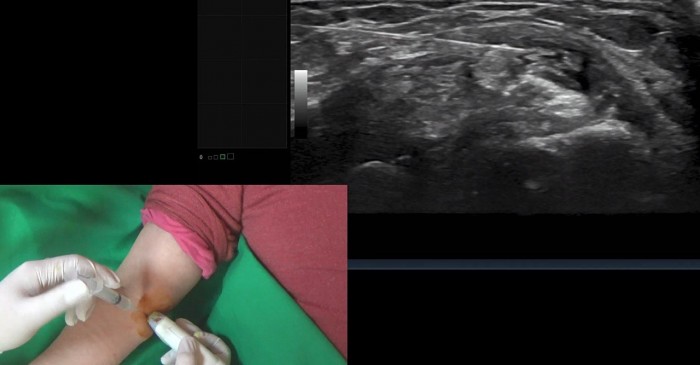

특히 오명진 대한한의영상학회 교육부회장이 강사로 나선 이번 교육에서는 일차 진료에서 흔히 볼 수 있는 근골격계 질환에 대한 초음파 활용에 초점을 맞춰, 각 부위마다 초음파로 보는 경혈의 정상 모습과 비정상 소견, 초음파 유도하 침술 영상을 소개하고 있다.

또한 효과적이고 안전한 약침 시술이라는 교육취지에 맞게 경혈 주위의 피부(皮膚), 혈맥(血脈), 신경(神經), 근건(筋腱), 관절(關節) 등의 해부학적 구조가 초음파 영상에서 어떻게 보이는지를 각종 일러스트를 통해 자세하게 다루고 있는 것은 물론 임상 증례를 통해 고위험 지역에서 내부 장기와 큰 신경 및 혈관의 위치를 확인해 안전한 경로로 약침을 시술하는 영상을 제공하는 등 실제 임상 현장에서 즉시 활용할 수 있다는 실용성에 큰 관심이 쏠리고 있다.

이와 관련 오 부회장은 “경락 경혈학은 고대의 표면 해부학으로, 학부 교과과정에서부터 경혈의 해부학적 지식을 교육하고 있다”며 “과거에는 손으로 촉진해 민감하게 압통 반응이 나타나는 아시혈(阿是穴)을 탐색했지만, 이제는 초음파를 통한 영상관찰로 직접 혈 자리를 확인할 수 있으며 이러한 행위는 현대 한의학적 진단법인 절진의 확장에 해당한다”고 강조했다.

오 부회장은 이어 “보다 효과적이고 안전하게 약침을 시술하기 위해서는 경혈의 위치를 정확하게 확인하고, 경혈 주변의 위험한 구조물을 피할 수 있어야 한다”며 “이런 점에서 초음파는 한의 임상영역에서 반드시 필요하다”고 거듭 강조했다.